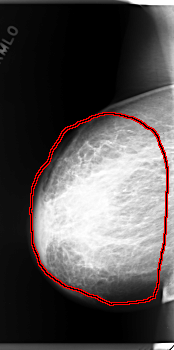

C_0159_1.RIGHT_MLO

FILE: C_0159_1.RIGHT_MLO.OVERLAY

TOTAL_ABNORMALITIES 1

ABNORMALITY 1

LESION_TYPE MASS SHAPE IRREGULAR MARGINS ILL_DEFINED

ASSESSMENT 5

SUBTLETY 5

PATHOLOGY MALIGNANT

TOTAL_OUTLINES 1

BOUNDARY